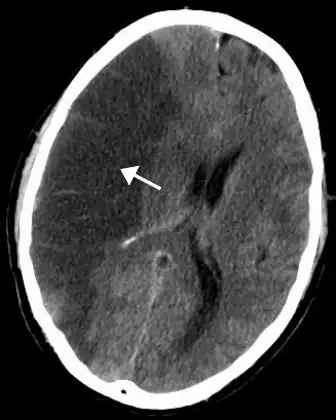

- Intracerebral haemorrhage is bleeding directly into the brain rather than around the brain.[42] Causes and risk factors include hypertension, blood thinning medications, trauma, and arteriovenous malformations.[49]